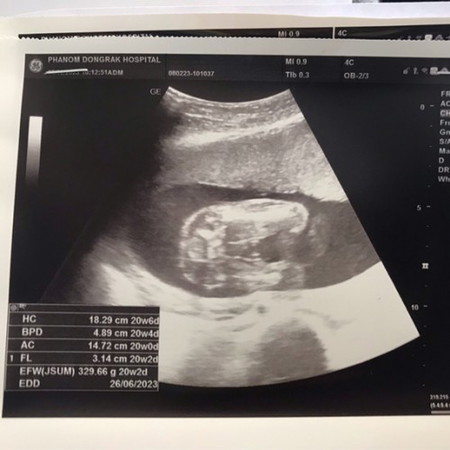

แม่ๆช่วยดูหน่อยค่ะว่าหัวอยู่ตรงไหน พอดีสีภาพจางมากดูไม่รู้เรื่องเลย🤣😅🥹

ดูเหมือนน้องจะเป็นหนุ่มน้อยเลยค่ะแม่ ^^

อันนี้ภาพใต้หว่างขาค่ะ

ภาพขาวดำจะเห็นกระดูกอวัยวะข้างในดธยากนิดนึงแม่

ได้ลูกชายแน่เลยค่ะ😂

เห็นแต่จู๋น้อยค่ะ 😂